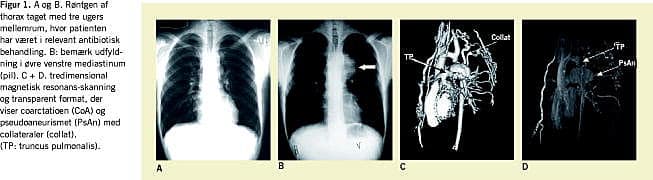

En 18-årig mand blev indlagt efter ti dages febrilia, opkastninger, ledsmerter og hævelse af højre ankelled. Tolv dage tidligere havde han bidt sig i tungen med efterfølgende halvanden times kraftig blødning. Objektivt fandt man blodtryk (BT) på 140/65 mmHg, puls 96, temperatur 39,3°C. Ved stetoskopi hørtes en systolisk mislyd over prækordiet med udstråling til carotiderne. Der blev beskrevet pulse i aa radiales og aa dorsales pedes. Paraklinisk fandt man C-reaktivt protein på 148 og leukocytter på 20,5. Et elektrokardiogram viste sænkningsreaktion uden tegn på venstre ventrikel-hypertrofi. Ankelledet punkteredes uden positive fund. Intravenøs behandling med penicillin 5 MIE ×4 og gentamycin 120 mg×2 blev påbegyndt og senere skiftet til diclosil efter bloddyrkningssvar (staphylococcus aureus ). Ekkokardiografi udført på et lokalsygehus gav mistanke om endokarditis på tricuspidalklap, og patienten blev henvist til Rigshospitalet til transtorakal (TTE) og transøsofageal ekkokardiografi (TEE). Endokarditis kunne ikke bekræftes, men antibiotikabehandlingen blev anbefalet fortsat på lokalsygehuset. Patienten blev udskrevet tre uger efter indlæggelsen med normalt resultat af røntgenundersøgelse af thorax (Figur 1A ) til intravenøs antibiotisk behandling foretaget af en hjemmesygeplejerske. En måned senere klagede patienten over hoste og synkebesvær. En røntgenundersøgelse af thorax viste nu nytilkommen breddeøget øvre mediastinum (Figur 1B). En efterfølgende computertomografi (CT) med kontrast (Figur 1C) viste betydelig dilateret aorta, der begyndte før arcus, bredte sig til efter arcus og målte 8 ×10 ×7cm. Patienten blev overflyttet til Cardiologisk Afdeling på Rigshospitalet. Han var upåvirket, uden smerter og havde et BT på 180/80 mmHg. Ved stetoskopi hørtes fortsat kraftig systolisk mislyd over prækordiet. Der blev beskrevet normal puls i ekstremiteterne. TTE viste ingen forandringer i hjertet og i de første 3-4 cm af aorta. Man havde således stadigvæk ingen forklaring på den systoliske mislyd. Infektionsparametre var normaliserede. Mistanke om usurer ved eftergranskning af røntgenoptagelsen af thorax og en meget lille aorta descendens på CT'en vakte endelig mistanke om CoA. Ved fornyet objektiv undersøgelse føltes nu ingen puls i femoralarterierne! Ny TTE og magnetisk resonans (MR)-skanning (Figur 1C+D) bekræftede mistanken om CoA kompliceret med et aneurisme og store kollateraler til aortaaneurismet. Ved akut venstresidig torakotomi fandtes CoA på det typiske sted lige efter venstre a. subclavia med kun to millimeters åbning og direkte herunder en 1-2 cm stor åbning til et mykotisk pseudoaneurisme beliggende i venstre lunges overlap. Selve aneurismet målte 10 cm. Distale aorta descendens målte 8 mm. Ved operationen blev CoA og aneurismet reseceret, og aorta descendens blev rekonstrueret med en rørprotese. På den første postoperative dag var patienten uklar og havde nedsat kraft og sensibilitet i højre arm. Symptomerne remitterede dog hurtigt, og patienten blev udskrevet i velbefindende otte dage efter operationen med metoprolol mod hypertension.

Denne voksne patient havde coarctatio aortae, en medfødt hjertesygdom, kompliceret ved endarteritis med stafylokokker og et mykotisk pseudoaneurisme. Patienten gennemgik en omfattende udredning, før diagnosen blev stillet. Først da det voksende aneurisme henledte opmærksomheden på aorta descendens blev mistanken om CoA vakt. Ved flere ekkokardiografier afsløredes CoA eller det voksende aneurisme ikke. Ved en CT påvistes aneurismet og en meget lille aorta descendens, hvilket faktisk var det, der gav mistanke om den rette diagnose. Ved TTE udført efter at mistanken var rejst påvistes CoA, og en MR-skanning gav den endelige og fulde diagnose.